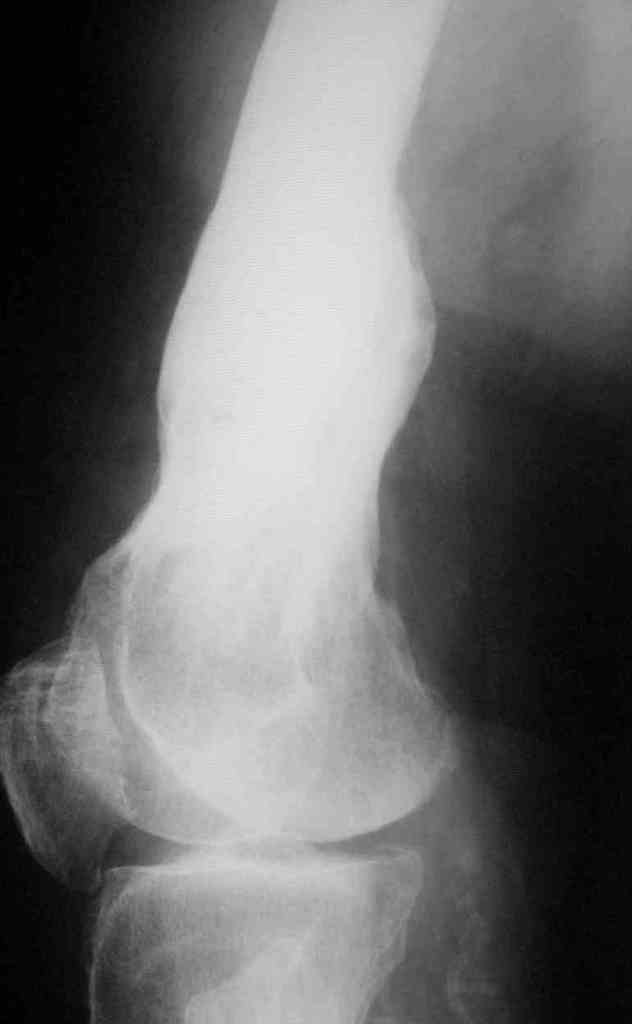

Укорочение правого бедра

Пациент 69 лет. лечился по поводу перелома н/3 левого бедра много лет назад: несостоятельность внутреннего синтеза - АВф- хр. остеомиелит, свищевая форма с периодическими рецидивами.

Результат - укорочение левого бедра 8 см.

Спасибо.В приложении рентгенограммы и внешний вид бедра.